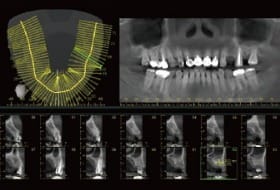

STEP 1 擬定客製化治療計畫

透過3D電腦斷層掃描,呈現骨頭立體影像植體與牙齒的360度視角,經專業醫師評估後,提供最適切的客製化治療計劃。